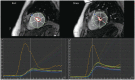

This document is the third part of the guidelines for the protocol, the interpretation and post-processing of cardiac magnetic resonance (CMR) studies. These consensus recommendations have been developed by the Consensus Committee of the Korean Society of Cardiovascular Imaging to standardize the requirements for image interpretation and post-processing of CMR. This third part of the recommendations describes tissue characterization modules, including perfusion, late gadolinium enhancement, and T1- and T2 mapping. Additionally, this document provides guidance for visual and quantitative assessment consisting of "What-to-See," "How-To," and common pitfalls for the analysis of each module. The Consensus Committee hopes that this document will contribute to the standardization of image interpretation and post-processing of CMR studies.